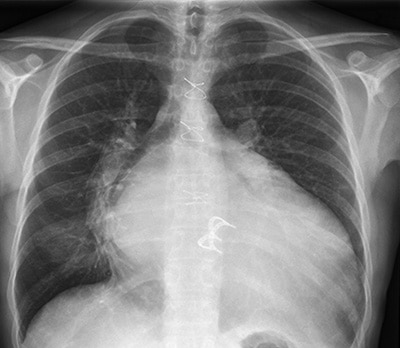

سی تی اسکن قلب یکی از روش های تشخیصی دقیق و آسان بیماری سرخرگهای کرونر قلب (CAD)، آزمایشهای پزشکی هسته ای می باشند که مهمترین و متداول ترین نوع آنها تصویربرداری (اسکن) پرفیوژن میوکارد است.

در سی تی اسکن قلب از یک ماده رادیو اکتیو بی خطر ، خون رسانی به عضله قلب در دو حالت ورزش و استراحت بطور جداگانه مورد بررسی دقیق قرار می گیرد.

پس برای بررسی دقیق تر وضعیت خون رسانی به عضله قلب بهتر است قلب را در شرایط فشار بررسی کنیم تا آن منطقه که دچار افت نسبی جریان خون (ایسکمی) به علت تنگی سرخرگی است با اسکن قلب خود را بهتر نشان دهد .

در این صورت با تشخیص منطقه مبتلا به افت جریان خون ، با سی تی اسکن قلب بطور غیر مستقیم سرخرگ مبتلا به تنگی را شناسایی کرده و با درمان بموقع تنگی ، از پیشرفت بیماری و خطرات بعدی پیشگیری خواهد شد. بنابراین اسکن قلب باید با آزمون ورزش انجام شود. آزمون ورزش که حداکثر نیم ساعت بطول می انجامد یا با دوچرخه و یا با دستگاه تردمیل ( Treadmill) انجام میشود.